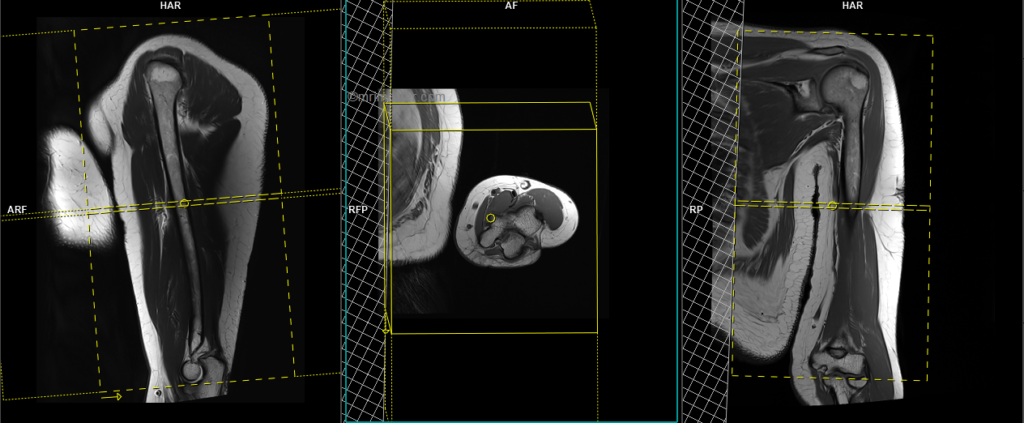

T2 stir axial 3mm SFOV

Plan the axial slices on the coronal plane and angle the planning block perpendicular to the humerus. Check the planning block in the other two planes. An appropriate angle must be used in the sagittal plane (perpendicular to the humerus). Slices must be sufficient to cover the whole upper arm from the acromioclavicular joint to the elbow joint. Adding saturation bands over the chest will help reduce breathing artifacts. The phase direction must be anteroposterior to avoid wrap-around and motion artifacts from the chest.

Parameters

TR 4000-6000 | TE 110 | FLIP 160 | NEX 2 | SLICE 6 MM | MATRIX 256X256 | FOV 170-200 | PHASE A>P | GAP 10% | TI 150 |